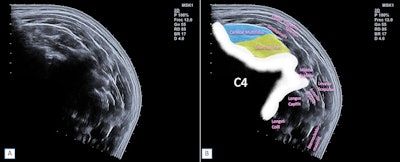

Panoramic ultrasound offers a wider field of view than standard B-mode ultrasound is able to obtain. For example, panoramic ultrasound can display both thyroid gland lobes on a single image, which could further help in diagnosing diseases and disorders. However, for this method to be successful, transducer movement and speed must be constant to avoid imaging deformations, according to the researchers.

Valera-Calero and co-authors wanted to compare several morphology indicators and average echointensity in muscles via panoramic and conventional B-mode ultrasound images. For the study, the team included 46 healthy volunteers and used ultrasound imaging on the cervical multifidus muscle and short rotator muscles. The indicators the team looked at included area, perimeter, circularity, aspect ratio, and roundness.